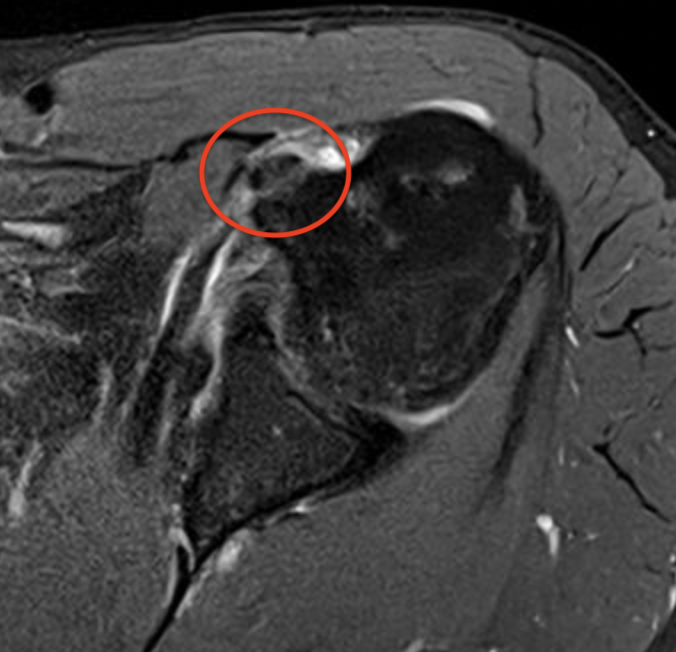

MRI

Medial Subluxation

Medial subluxation with subscapularis tear

Kang et al Skeletal Radiol 2017

- accuracy of MRA for 100 patients with LHB subluxation at arthroscopy

- 83% sensitive